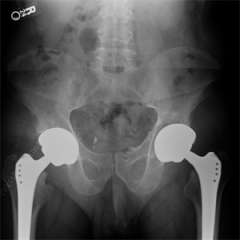

UCLA Joint Replacement Service surgeons are experts in the spectrum of joint replacement procedures for the hip and knee. Surgical treatment often involves a total joint reconstruction/joint arthroplasty. For the knee this may involve unicompartmental knee replacement or total knee replacement. A small subset of patients may be candidates for a bone realignment procedure called an osteotomy. For the hip, treatment may involve a bone-conserving surface replacement procedure or a total hip replacement. A total hip replacement replaces your damaged hip joint with an artificial one. The surgical procedure can be performed from behind the hip, to the side of the hip, or from the front of the hip. We have experts who perform the Anterior Hip Replacement surgery. Again, a small subset of patients may be candidates for osteotomy procedures.